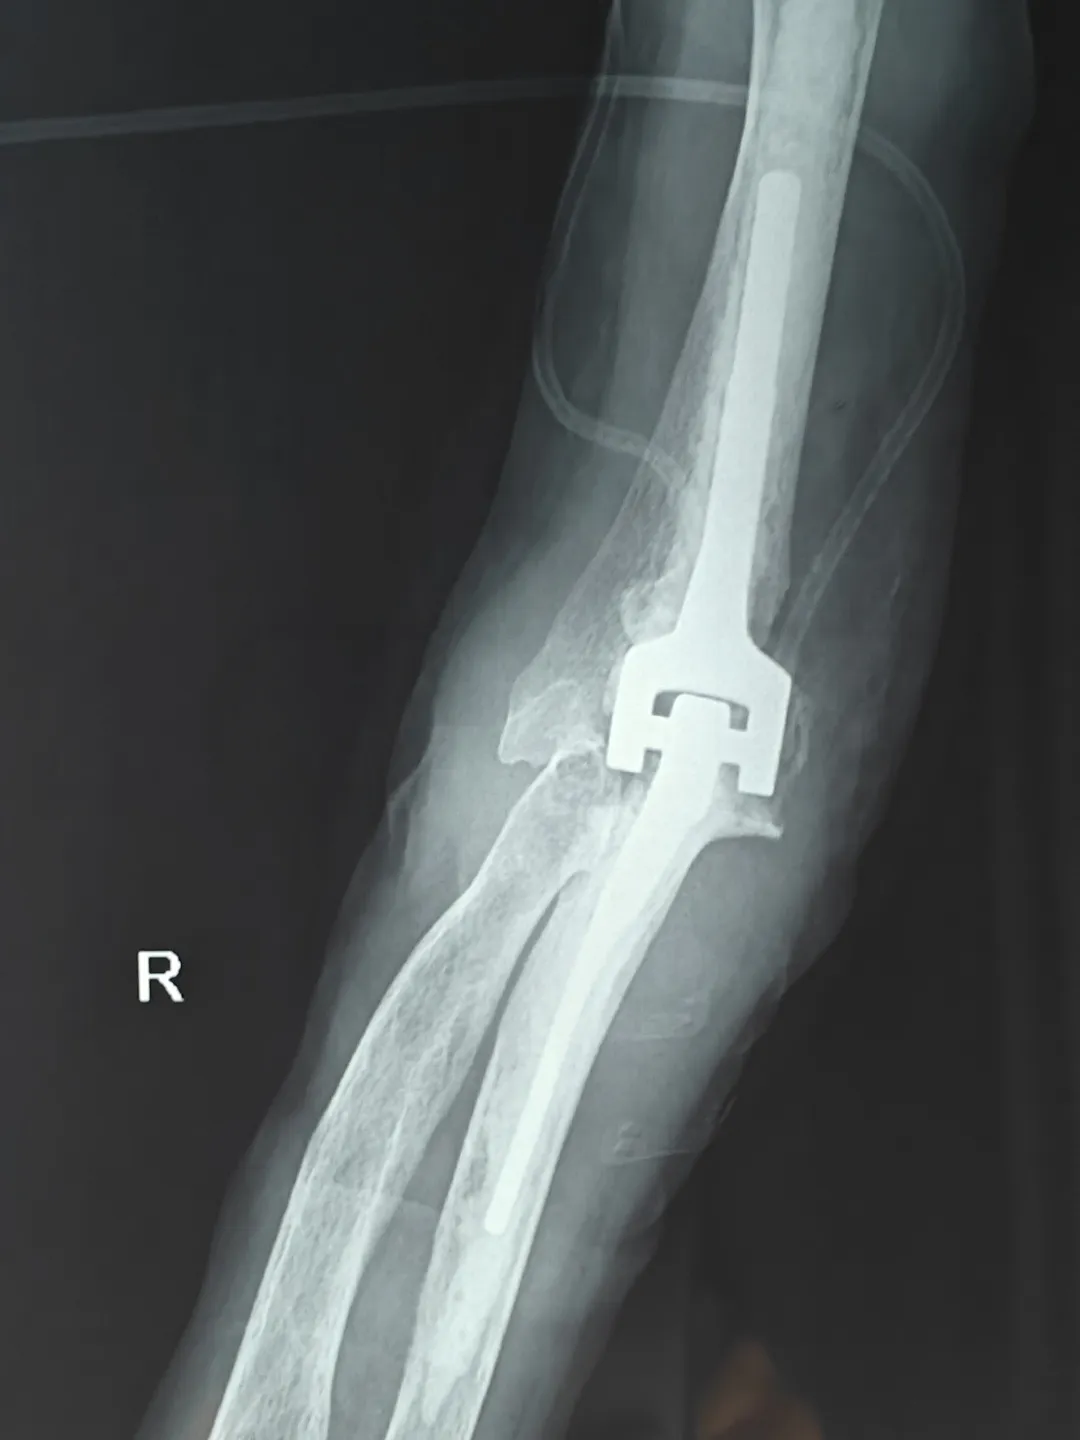

在李庭教授的指导下,91直播 创伤外科中心A区医护团队成功为患者实施手术。术后,患者一直积极配合医生的治疗方案,并严格遵守康复计划。通过一系列的康复训练和物理治疗,患者的身体状况逐渐好转,各项生理指标也逐渐恢复正常。

患者术后X光片

北京积水潭医院知名创伤骨科专家李庭教授,作为91直播 外聘教授,高度重视91直播 创伤急救外科学科建设,亲临91直播 进行全肘人工关节置换术的教学手术。整个手术过程行云流水,从细致的术前准备,到精确的手术操作,再到细致的术后管理,体现出李庭教授极高的专业水准和精益求精的手术理念。李庭教授每做一步都会对91直播 医生详细讲解,将多年的临床经验毫无保留地分享,这种传帮带的学术精神令人敬佩。李庭教授精湛的技术和丰富的经验,为91直播 创伤急救外科医生团队带来了难得的学习机会,规范了诊治流程,增加了四级手术率,同时也让患者和家属倍感安心。